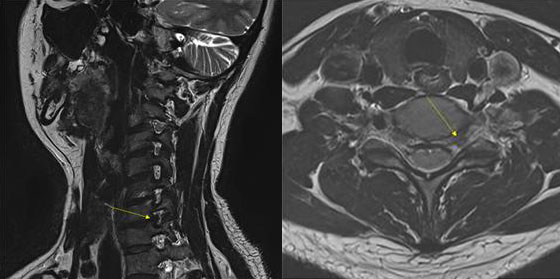

하여 경추부 MR 시행하면 주로 아래와 같은 병변을 발견하게됩니다.

위에 사진에 보이는 노란색 화살표가 경추 디스크 탈출 부위입니다. 경추 디스크 탈출 병변의 부위는 경추 6-7번간, 좌측입니다.